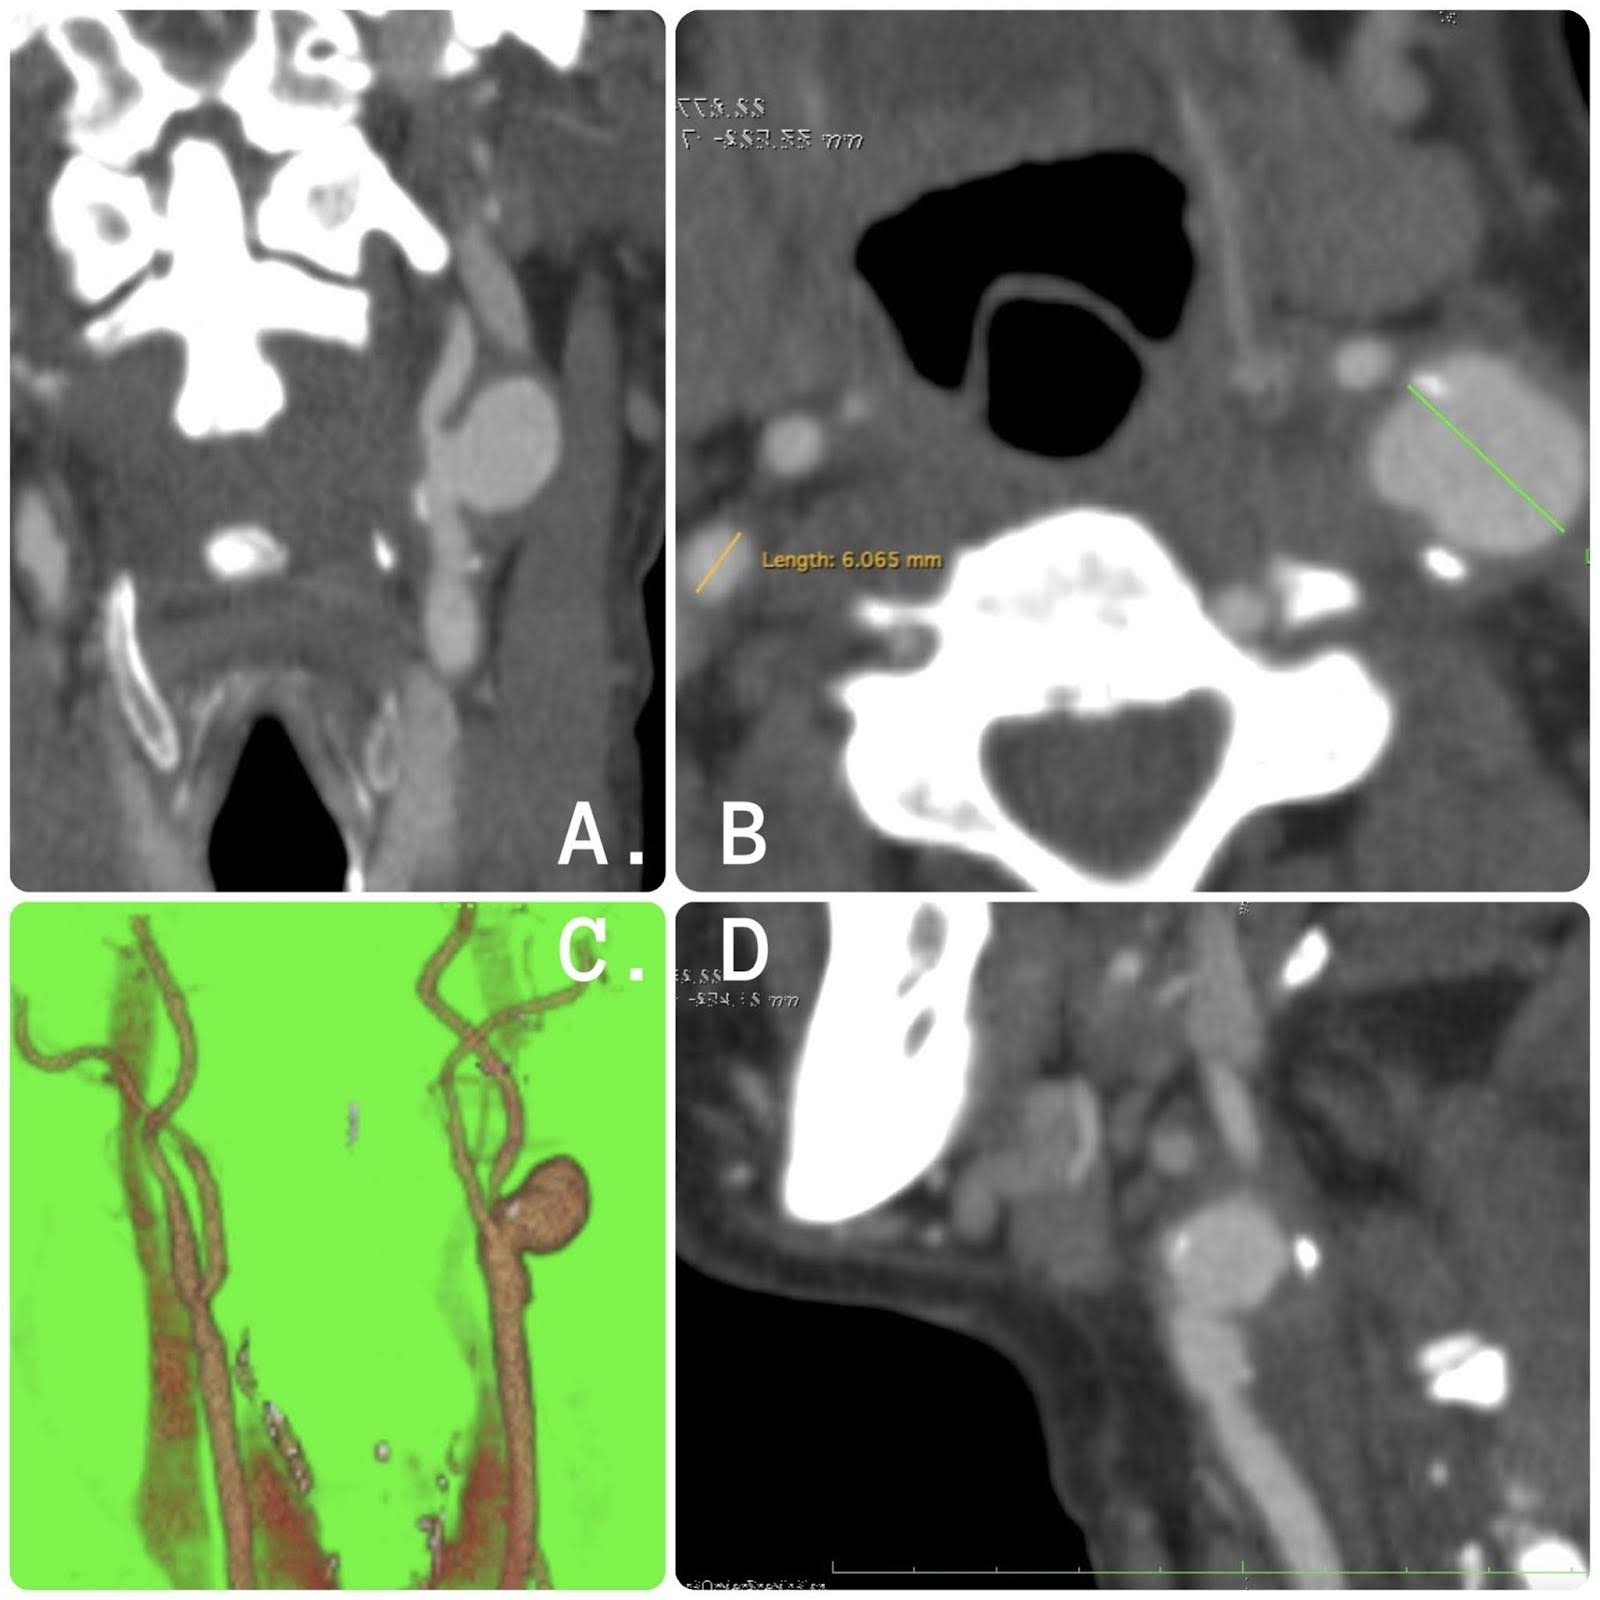

Die Angiotomographie des Patienten zeigt folgenden Befund: linke innere Halsschlagader mit einem sackartigen Aneurysma von 1,8 cm im größten Durchmesser, das vor der Operation auf den proximalen Teil der Bifurkation beschränkt ist. Die Bildgebung der Patiententomographie ist in Abbildung 1 zu sehen.

Abbildung 1. Tomographie-Bilder. (A) Koronaler Schnitt mit Nachweis eines Aneurysmas der linken Arteria carotis interna mit sackförmiger Morphologie. (B) Axialer Schnitt mit Nachweis eines Aneurysmas der linken Arteria carotis interna mit einem Durchmesser von 1,8 cm. (C) Dreidimensionale Rekonstruktion. (D) Sagittaler Schnitt mit Nachweis eines Aneurysmas der linken Arteria carotis interna mit atherosklerotischer Plaque.

Wir müssen uns daran erinnern, dass die Computertomographie-Angiographie (CTA) im Falle eines hohen klinischen Verdachts ein "Gold"-Standard für die Diagnose von Aneurysmen und die Definition anatomischer Strukturen ist.

Aneurysmen, die sich hoch in der distalen Arteria carotis interna (ICA) befinden, wie sie bei einer stumpfen Dissektion der Halsschlagader auftreten, werden im Ultraschall notorisch übersehen. Solche Aneurysmen erfordern einen hohen Verdachtsindex, der zu einer zusätzlichen Bildgebung mit Tomographie führt, und haben den Vorteil, dass sie Knochenbeziehungen und anatomische Orientierungspunkte sichtbar machen, die entscheidend für die Entscheidung sind, ob eine Läsion als "chirurgisch unzugänglich" gilt und einen endovaskulären Eingriff erfordert. 6-7